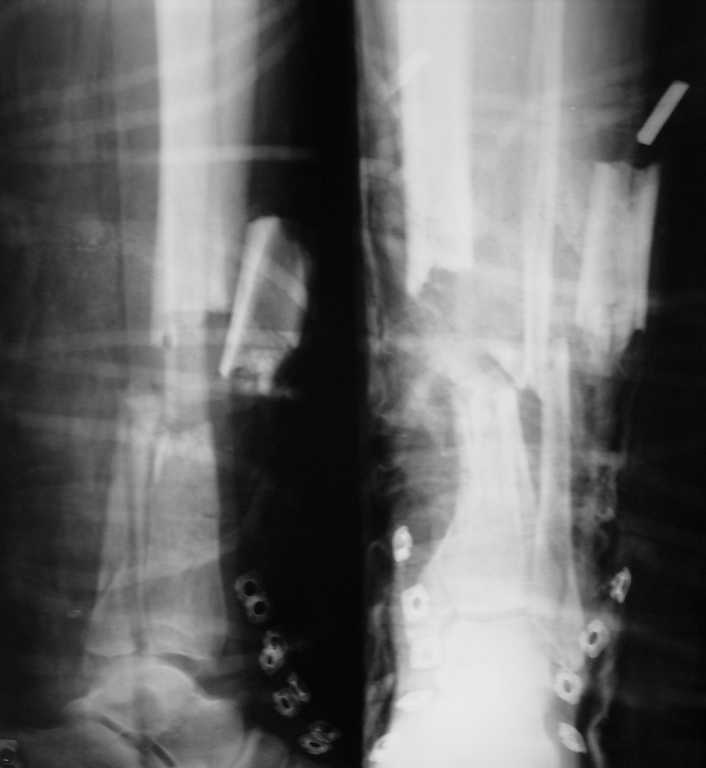

открытый многооскольчатый перелом костей голени |

больной 38 лет, бытовая травма, доставлен через 30 мин после травмы.

если можно, хотелось бы получить рекомендации по оптимальному методу лечения данного перелома.какие будут мнения?